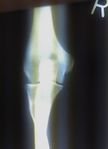

| Joint | From | To | Description |

| humeroulnar joint | trochlear notch of the ulna | trochlea of humerus | Is a simple hinge-joint, and allows of movements of flexion and extension only. |

| humeroradial joint | head of the radius | capitulum of the humerus | Is a hinge-joint joint. |

| proximal radioulnar joint | head of the radius | radial notch of the ulna | In any position of flexion or extension, the radius, carrying the hand with it, can be rotated in it. This movement includes pronation and supination. |